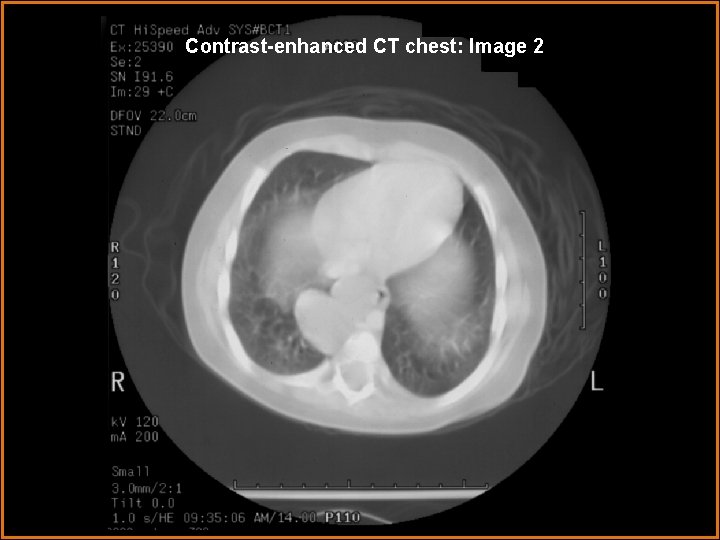

Contrast-enhanced CT chest: Image 2

Findings and Differentials Findings: - CXR PA and lateral: 2. 8 cm round opacity in right paravertebral region. - CT chest with contrast: Non-enhancing bilobular complex cystic lesion in the right posterior inferior mediastinum that displaces esophagus towards the left. 14 to 40 HU. - Barium swallow: Mass does not communicate freely with the esophagus. - MRI chest with and without contrast: Cystic lesion with internal septations without rim or mural enhancement. Lesion contacts the right hemidiaphragm medially, the lower thoracic vertebral bodies laterally, and the left atrium posteriorly. The posteromedial segment of the right lower lobe is displaced around the lesion. Differentials: • Bronchogenic cyst • Gastrointestinal duplication cyst